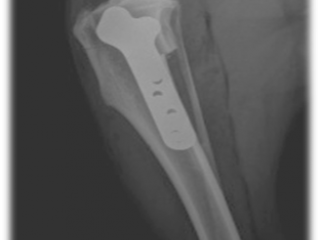

Arthroscopie d'un coude arthrosique

- Fractures: plaques vissées, plaques verrouillés, fixation externe de type JAM ou illizarov